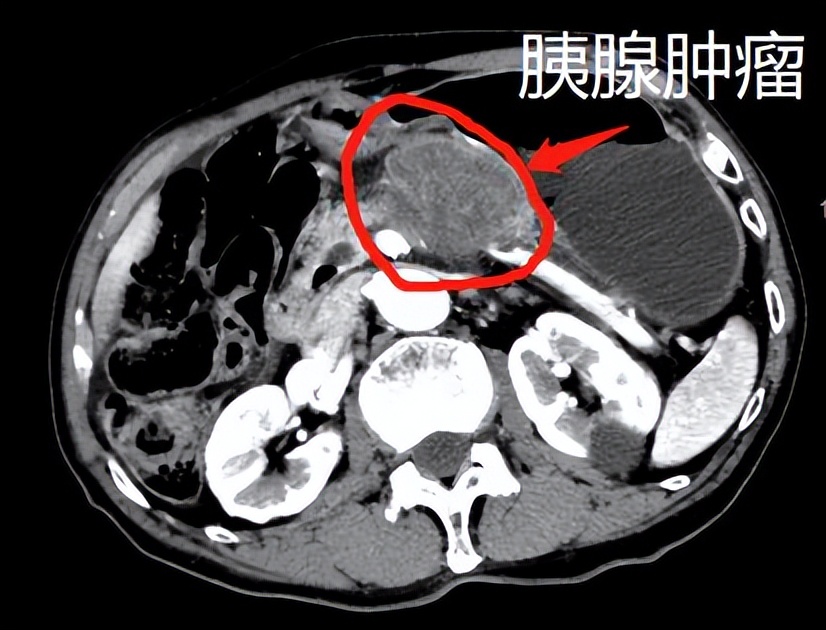

周三浦东院区门诊,91岁老爷爷前来复诊配药,缘由今年5月发现胰腺占位,当时家属考虑高龄原因,商量后决定保守治疗。看我门诊时老爷子精神状态挺好,性格开朗,之前和医院几乎没打过交道。 抱着对专业的“自信”我还是建议家属进行胰腺穿刺,没有病理诊断,很多治疗不能做,反之,穿刺取得切片病理确诊结果,即使口服化疗、免疫治疗也是有的放矢。 而且像老爷爷的肿瘤位置,超声引导下就可以穿刺,进针点局部麻醉,人始终保持清醒,5分钟左右,就可以把细胞取出,就一个小针眼,不需要缝针,痛苦几无。家属听完解释后,之前的疑虑基本消除,决定采取积极的穿刺和后续的治疗。

入院检查顺利完成胰腺穿刺,对91岁高龄不仅要保证没有并发症,更不能诱发心肺等疾病发生,次日出病理结果,确诊胰腺癌,做好治疗后顺利出院。3个月过去了,老人继续门诊治疗,各方面一直都很好,最近复查也稳定。

个人建议:发现胰腺占位,一方面要及早做好CT、PET-CT、肿瘤标记物等检查明确病灶和全身情况,一方面要做好开始治疗的心理准备,胰腺穿刺就是治疗的第一关,因为刚发现也比较着急,就像这位91岁老爷爷,超声引导胰腺肿瘤穿刺不仅可以快速高效明确诊断,也具有安全、痛苦小、全身反应小的优势,所以如果需要胰腺穿刺,也不要过于紧张,过程基本和这位91岁的老爷爷一样:安全、有效、创伤小。